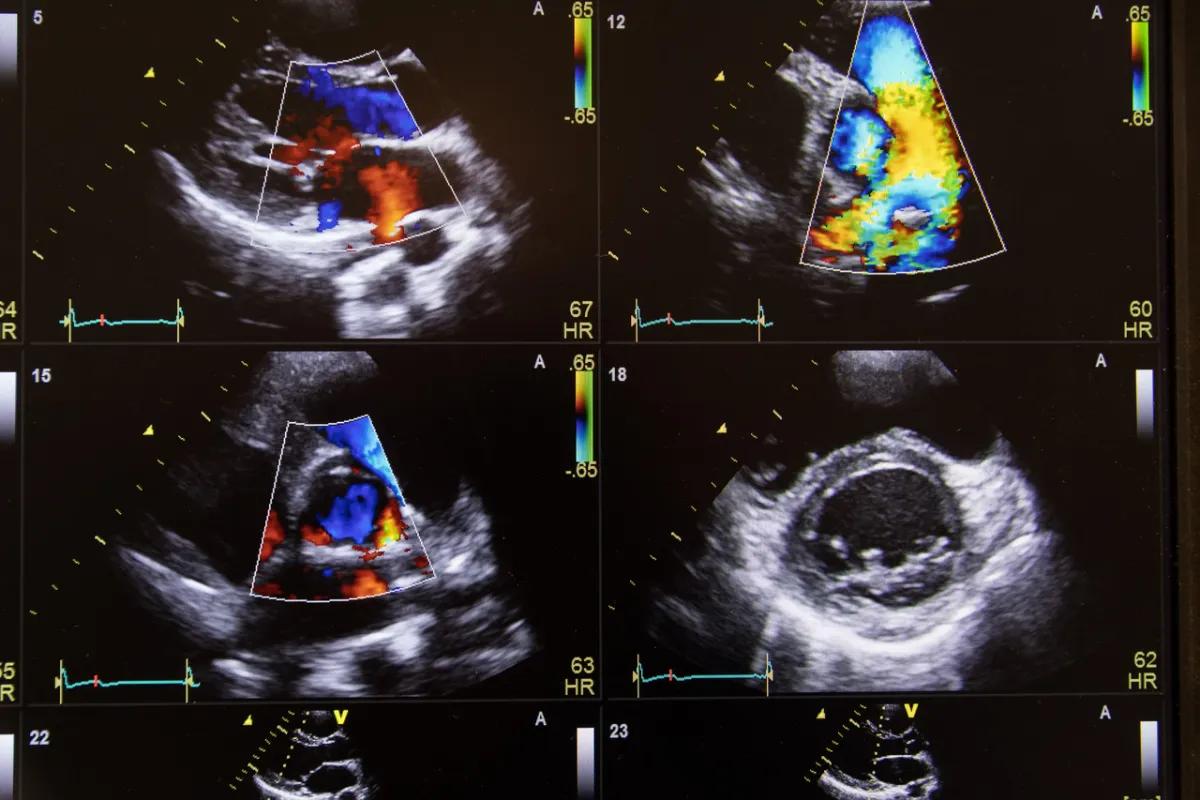

الموجات فوق الصوتية لأكياس المبيض

الموجات فوق الصوتية لكيس المبيض هي اختبار تشخيصي يستخدم لتقييم ما إذا كانت المرأة مصابة بخراجات المبيض، وهذه الأكياس التي تتكون في المبيض يمكن أن تكون حميدة ولا تسبب أي ضرر لصحة المرأة، وفي بعض الحالات تكون هذه الأكياس سرطانية، ويجب تشخيصها وعلاجها بالتدخل الجراحي، حيث يتم إجراء الموجات فوق الصوتية لكيس المبيض باستخدام محول الطاقة ثم يتم تحويلها إلى صور على شاشة الكمبيوتر. وعادة ما يكون الاختبار سريعًا وغير مؤلم.